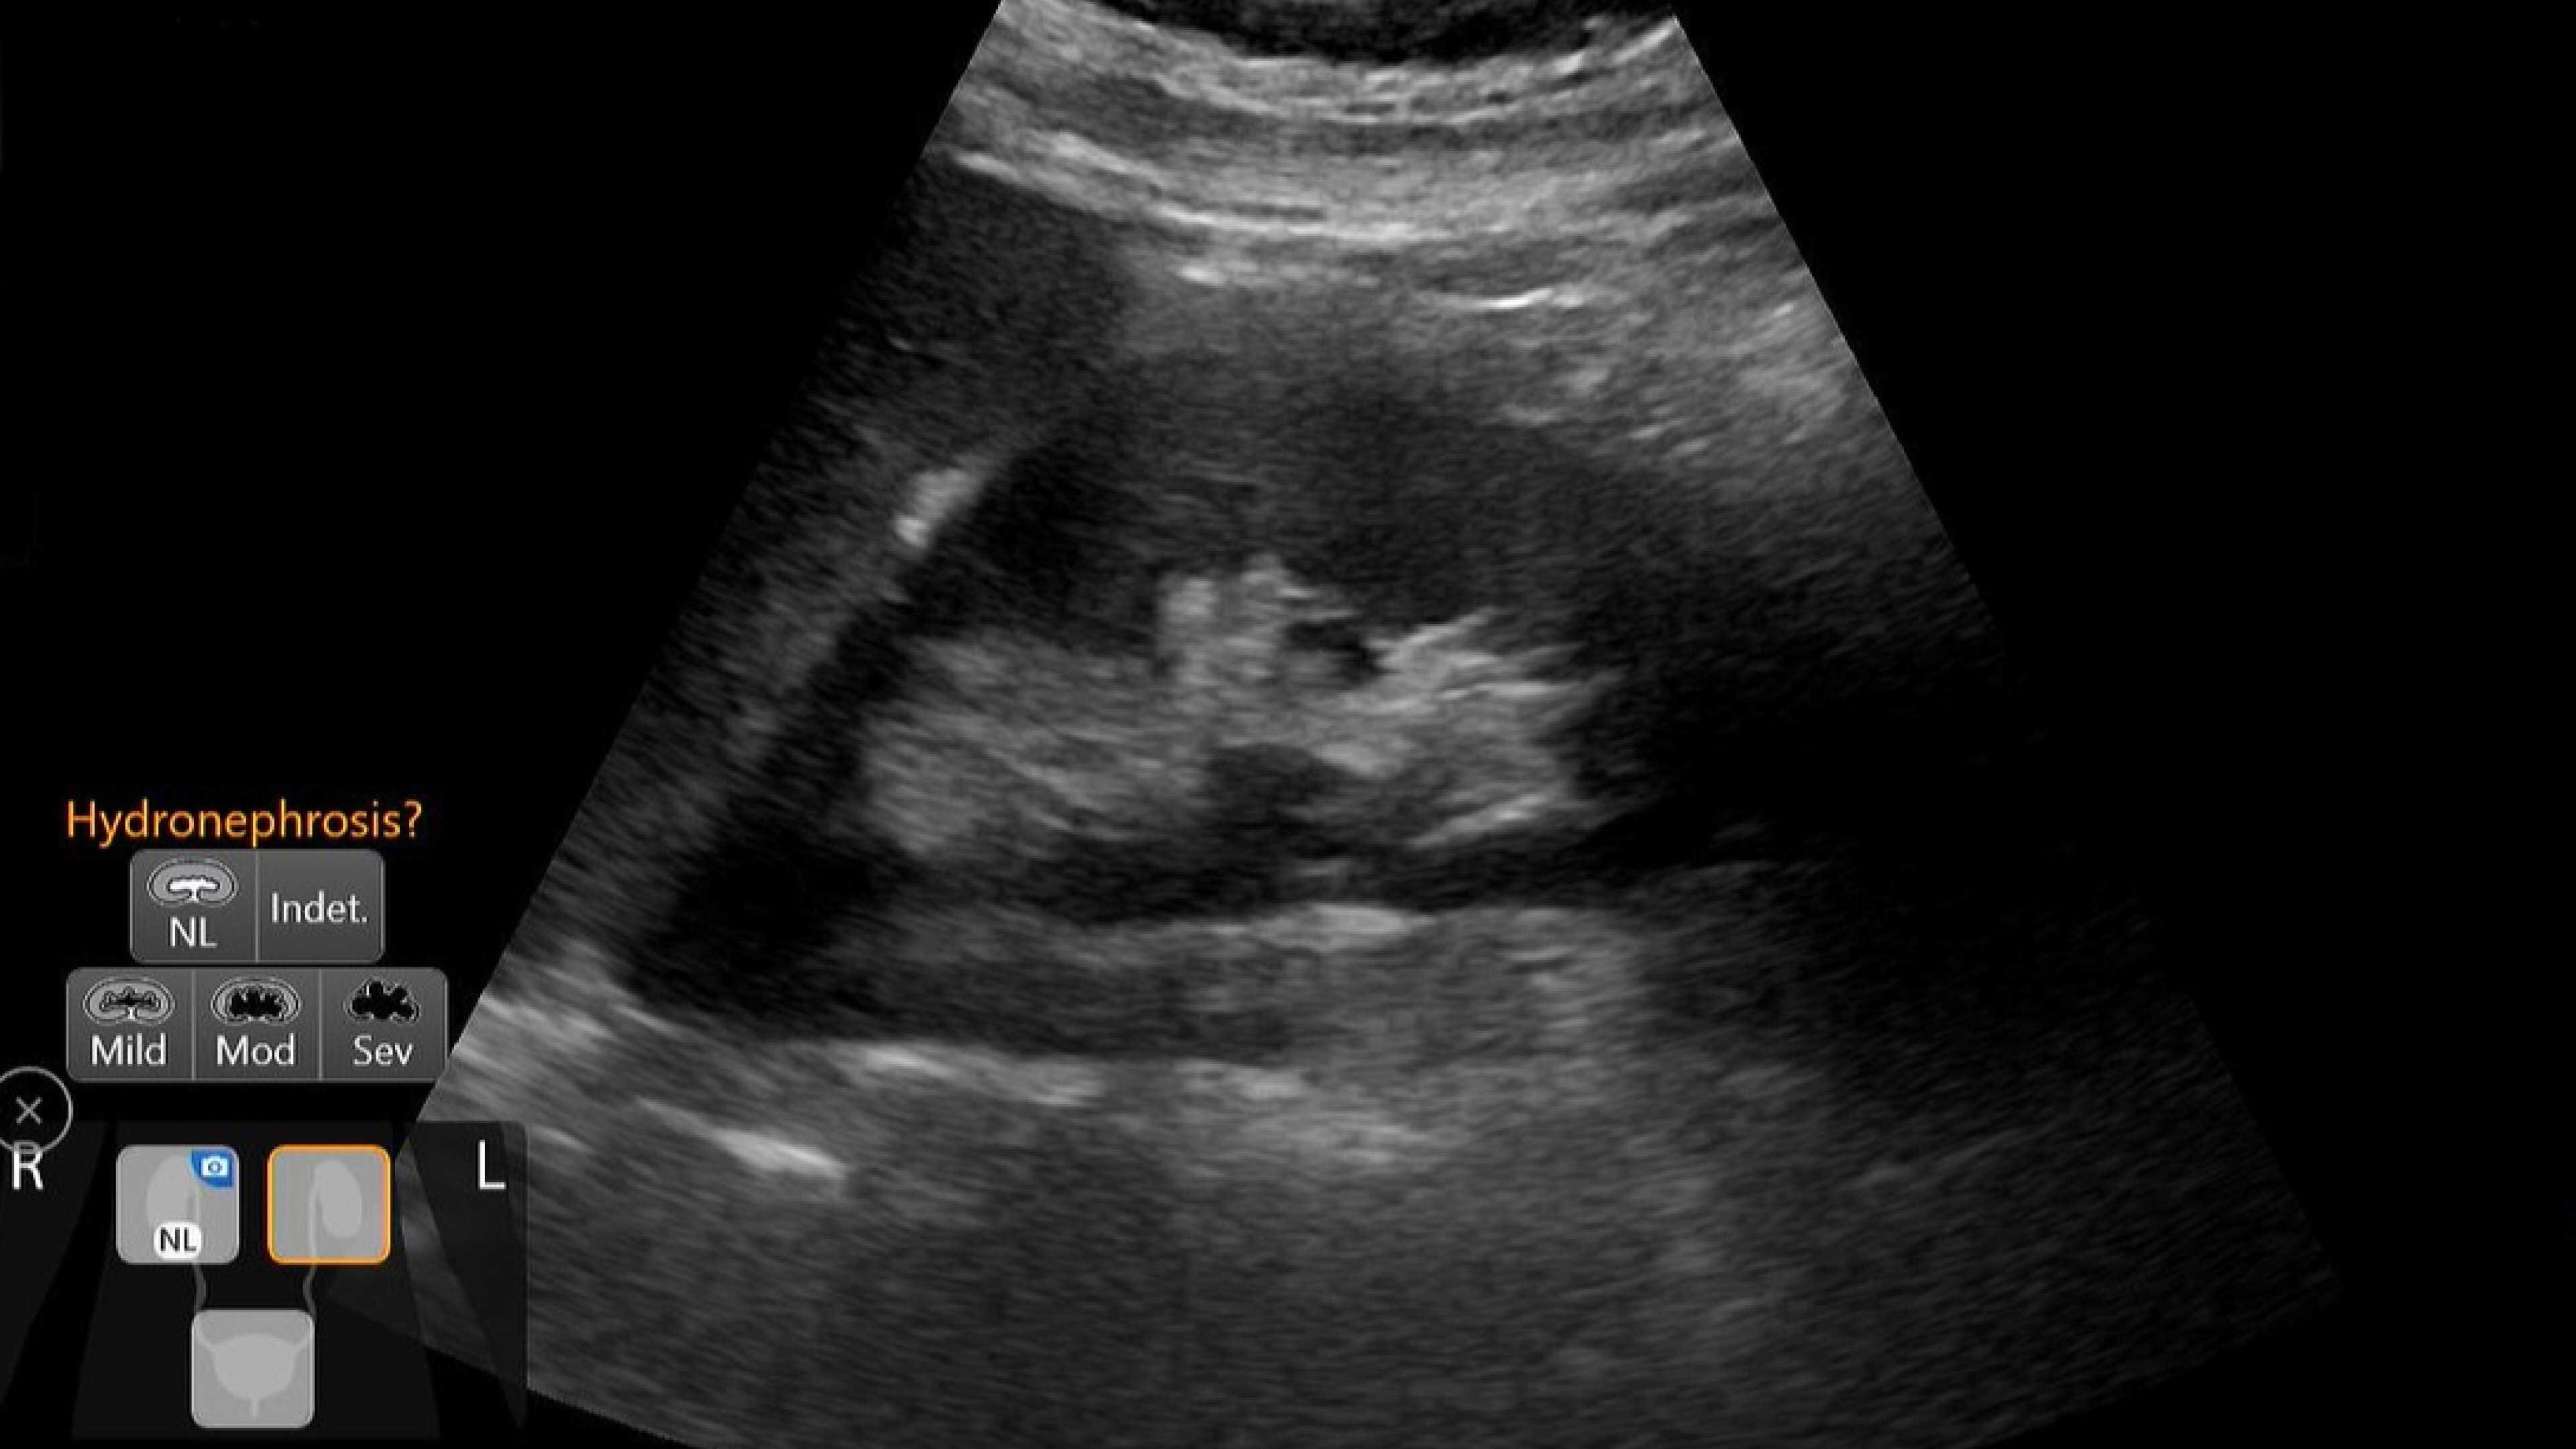

Venue Sprint™ gives you the uncompromised image quality and smart workflow of Venue™ family systems along with the freedom and maximum portability of wireless probes. This all-in-one, entry-level solution combines wireless connectivity with a small, streamlined console. It features Venue family software, to give you access to the AI tools you need, to simplify advanced exams whenever and wherever care is needed.

Critical care

Enables on-the-spot visual confirmation, aiding the team in decision-making and collaboration on complex cases.